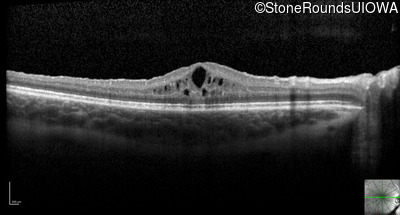

Optical Coherence Tomography - Right - 20/50 +2 sc

Exemplar / OCT Stack